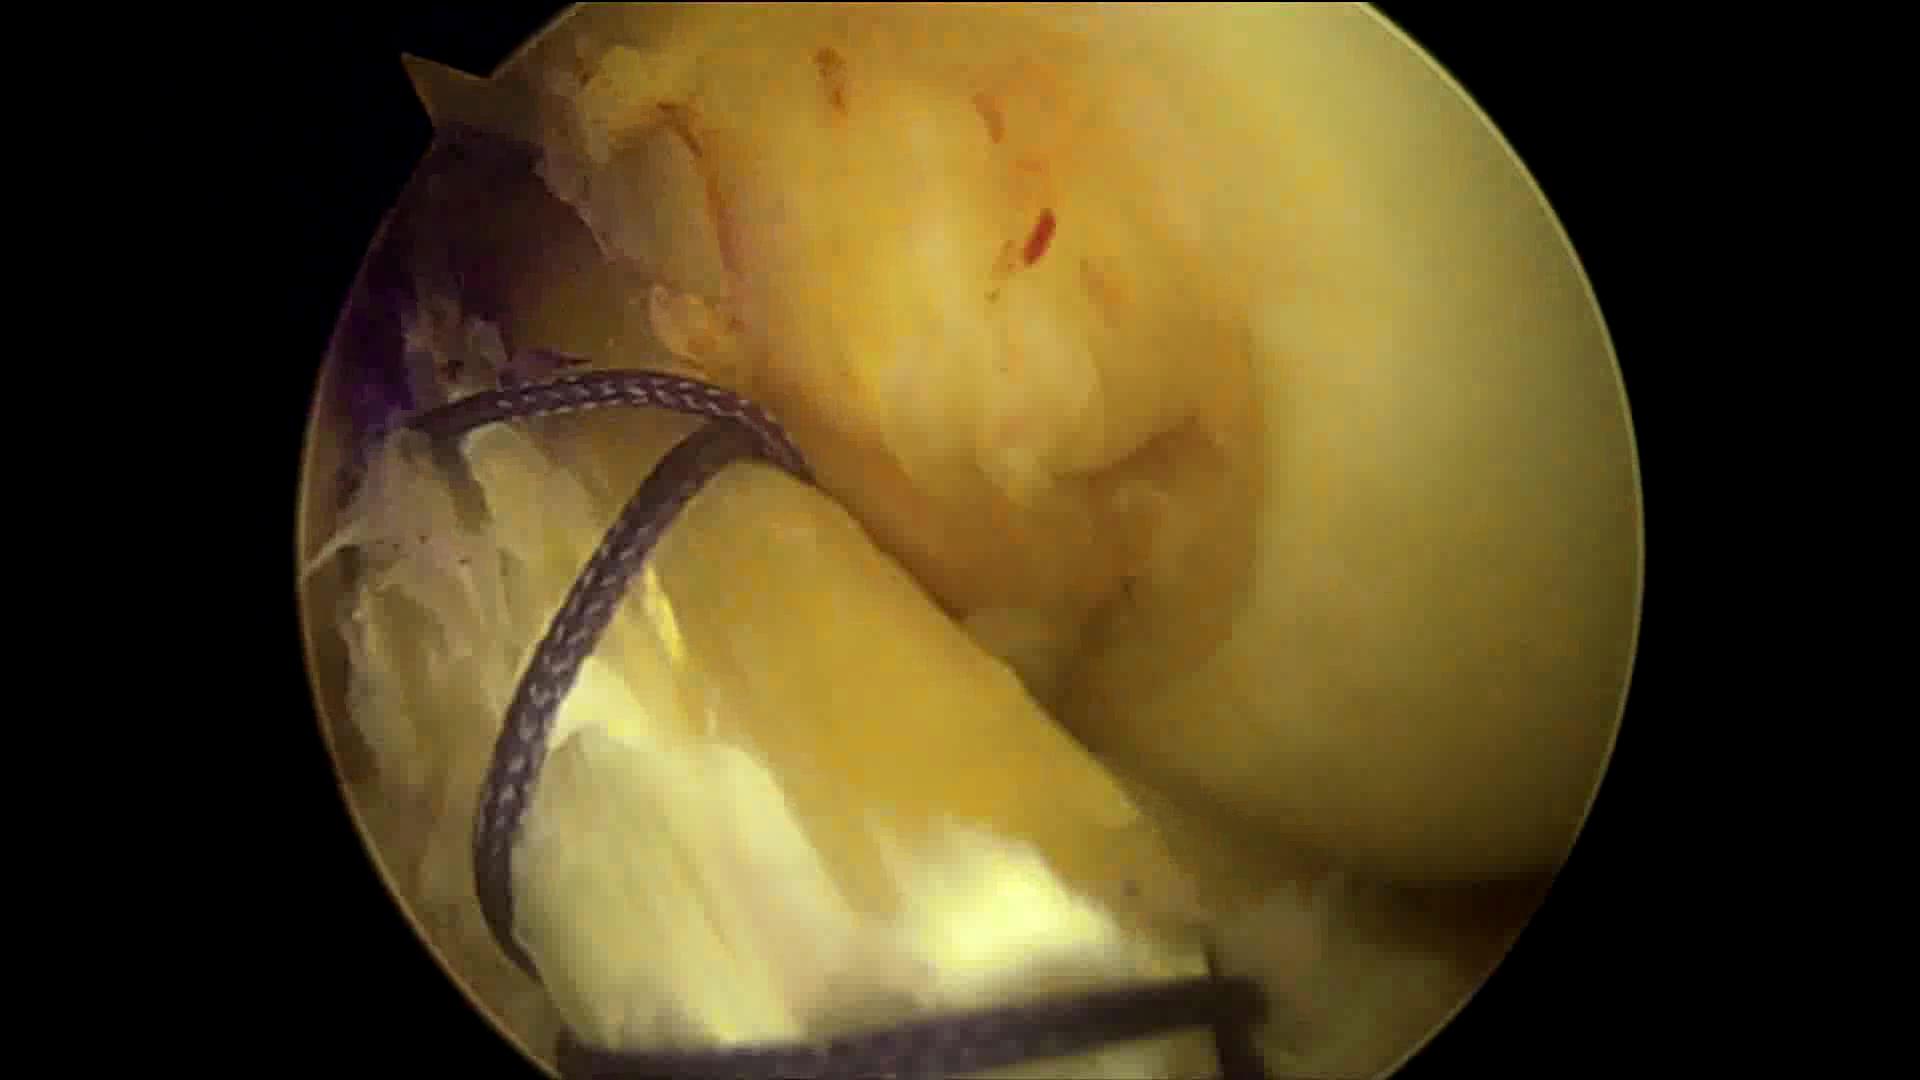

重建的前交叉韧带

因此,保残重建也是现在主流的手术方式!